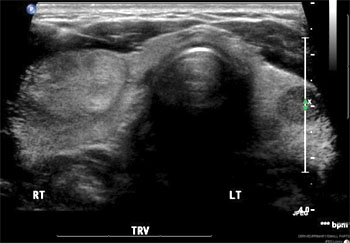

thyroid nodule Solid or fluid-filled lumps that grow in the thyroid gland are called nodules. More than 90 percent of thyroid nodules are benign (noncancerous).

These growths are common and affect about half of people aged 60 or older. Women are more likely than men to develop thyroid nodules. If you suspect you have a thyroid nodule, turn to the thyroid experts at Henry Ford Health System for an accurate diagnosis and effective treatment.